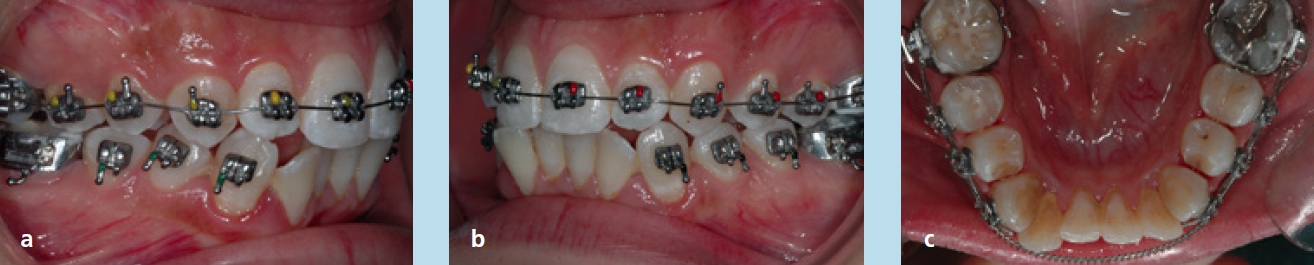

Für die Behandlung und geplanten Zahnbewegungen wurde eine festsitzende Apparatur (0,022 × 0,028 Slot-Brackets) eingegliedert; im Oberkiefer erfolgte eine vollständige Bebänderung, im Unterkiefer nur eine Teilbebänderung der Seitenzähne (Abb. 22a bis c). Aufgrund der Achsenstellung der Fronten im Unterkiefer sollte eine weitere labiale Kippung bei der Auflösung des Engstandes vermieden werden. Um dies weitestgehend umsetzen zu können, wurde im gesamten Frontzahngebiet und bei den seitlichen Zähnen inklusive der Mesialfläche der Unterkiefereckzähne um insgesamt 4 mm gestrippt (0,20 bis 0,25 je Approximalfläche). Die Form der Zähne und der Verlauf der Gingiva ließen dies zu. Zu Beginn der Behandlung wurden nur die 1. Molaren, Prämolaren und Eckzähne bebändert, um die Proklination der unteren Schneidezähne zu vermeiden. Die Prämolaren wurden jeweils von mesial und distal sowie die Eckzähne von distal mit dem oszillierenden EVA-Winkelstück mit Hubbewegung gestrippt. Für eine effektive Distalisation und Ausnutzung des gewonnenen Platzes wurde in den Bogen zwischen den Zähnen 33 und 43 eine Druckfeder eingesetzt (Abb. 23). Nach vollständiger Distalisation der seitlichen Zähne wurden die Schneidezähne beklebt. Vor dem Einligieren des Bogens wurde die Unterkieferfront von mesial und distal einschließlich der mesialen Fläche der Eckzähne gestrippt. Es wurden Lace-backs und voller Bogen eingesetzt (Abb. 24a bis c).